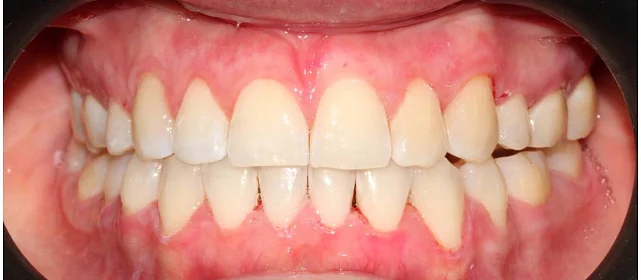

Зубы выровнены, смыкание нормализовано. Установлены несъёмные ретейнеры на обе челюсти, сняты сканы для ретенционных кап.

Решение: Поставили прозрачные элайнеры Click — начали с компактного набора из 20 кап. Основной комплект сделал основной объем работы, но для финальной доводки понадобился дополнительный набор из 10 кап. Итого 30 кап за 23 месяца. Результат — зубы на месте, смыкание в норме. Зафиксировали ретейнеры на обе челюсти, сняли сканы для ретенционных кап.